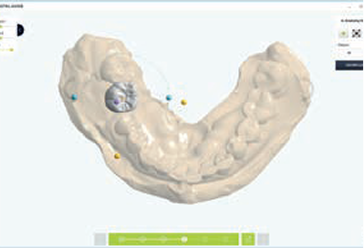

Surgical Guide Setting

Create Surgical Guide

Add Support Bar, Viewing Window

It takes at least one week to produce through a request from the center, but if you design your own using Dentium Digital Guide Software, you can produce it within 30 minutes to an hour. When weeding the guide, pay attention to the ct alignment, and when making the guide, the undercut and border should be well set to fit the patient's mouth. It is recommended to use the anchor pin function for stability.